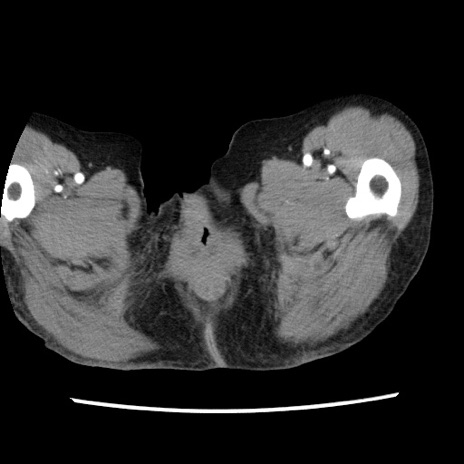

冠状断像